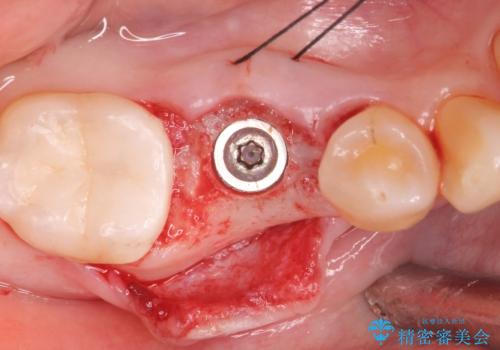

- 過去に抜けてしまった歯のところにインプラントを入れたいとの事で来院。

CTで確認したところ骨の高さや厚みがインプラント埋入できる状態でしたのでインプラント治療を行いました。

- インプラント体、アバット、仮歯、ジルコニアクラウン・42.9万円 e-maxインレー・7.7万円 費用は治療当時の料金となります